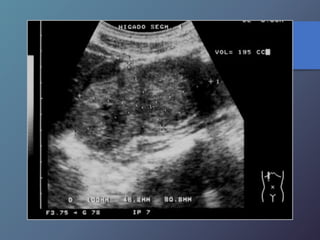

Cirrosis Hepática

Proceso difuso hepático caracterizado

por fibrosis y la conversión de la

arquitectura normal del hígado en

nódulos estructuralmente anormales.

• Redistribución de volumen. Índice

caudado/lob. Der. 0.65.

• Ecoestructura grosera.

• Superficie nodular.

• Nódulos de regeneración.

• Nódulos displásicos.

• Hipertensión portal: Ascitis, esple-

nomegalia, varices.

Características Ecográficas